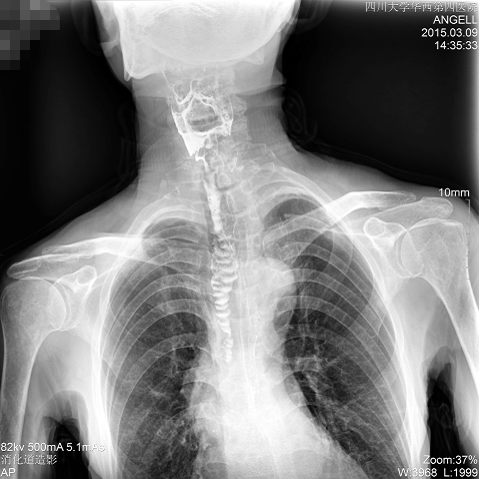

如下圖所示:該患者因吞咽時(shí)感到很難受,進(jìn)食時(shí)也經(jīng)??人怨示歪t(yī)診斷。使用多功能dr為病人進(jìn)行消化道造影診斷,要求他吞鋇后發(fā)現(xiàn),食道各段通過(guò)順利,形態(tài)規(guī)則,雙側(cè)梨狀窩不對(duì)稱左側(cè)稍淺,多次吞咽動(dòng)作后,仍見(jiàn)鋇劑滯留,并見(jiàn)鋇劑進(jìn)入氣管,屬于會(huì)厭征陽(yáng)性。會(huì)厭功能紊亂,鋇劑進(jìn)入了氣管。

圖為正位:通過(guò)動(dòng)態(tài)影像可以清楚看到鋇劑進(jìn)入了支氣管道且雙側(cè)梨狀窩不對(duì)稱

圖為斜位:通過(guò)動(dòng)態(tài)影像可以清楚看到鋇劑進(jìn)入了支氣管道

通過(guò)多功能dr可以診斷該病人的癥狀為會(huì)厭功能紊亂,鋇劑進(jìn)入到了氣管。而在動(dòng)態(tài)透視下可以清晰的觀察到鋇劑從何處進(jìn)入氣管,可清晰顯示食管粘膜結(jié)構(gòu)。使用多功能dr其獨(dú)特的視頻采集技術(shù),可實(shí)時(shí)保存視頻并能實(shí)現(xiàn)900萬(wàn)像素實(shí)時(shí)點(diǎn)片,才能獲取這樣清晰的病灶點(diǎn)。而常規(guī)dr只能拍攝靜態(tài)片,且成像效果大打折扣,因此較難確診病灶。